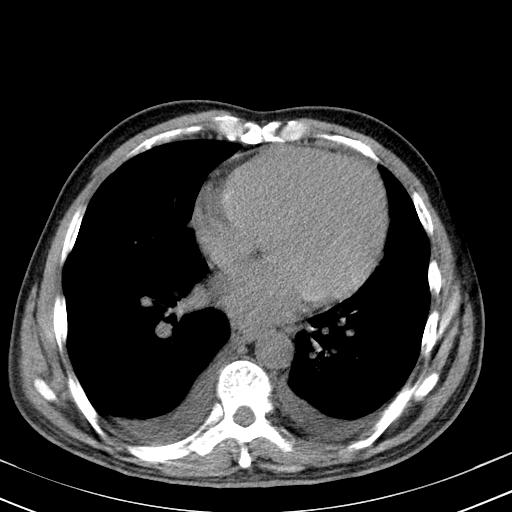

以下是引用zxl51642在2010-3-21 17:06:00的发言:[br]右下中心型肺癌并阻塞性肺炎/不张,纵膈淋巴结肿大,右侧大量胸腔积液,左侧少量胸腔积液,少量腹水。建议纤维支气管镜进一步检查。